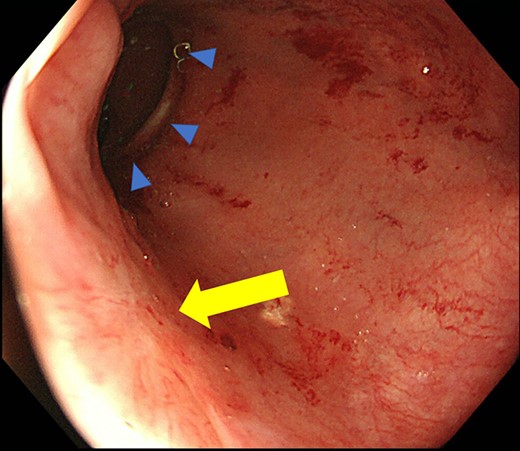

Case 2 was a 58-year-old man with a BMI of 30.3 kg/m2. Robot-assisted LAR and ileostomy was performed for lower rectal cancer over the past 2017 years, and a 1/2 circumferential fistula around the 6 o’clock direction was recognized on postoperative colonoscopy (Fig. 4). The patient was diagnosed as having a grade A anastomotic leakage without symptom because of the anastomotic leakage. He was discharged on POD 26 and was followed up on an outpatient basis. Contrast imaging performed simultaneously with endoscopic examination 6 months after the operation showed remarkable improvement of the abscess cavity, but it still remained (Fig. 5a and b). The anastomotic leakage improved 11 months after surgery (Fig. 6), but a polyp was found on the anal side 2 cm from the anastomotic site and was resected. Adenocarcinoma, pTX, ly0, v0, pHMX, and pVMX were diagnosed. The tumor was followed up because the depth of penetration, the deep stump, and the horizontal stump remained unknown (Fig. 7). Regarding the polypectomy site, no abnormality was found in the examination 8 months after resection of the polyp. Therefore, ileostomy closure was performed 18 months after the first operation (Fig. 8). Postoperatively, it took some time to improve the intestinal movement with paralytic ileus, but the patient was discharged 18 days after surgery. The Wexner score one month after closure was 18 points and still showed high anal dysfunction but the patient was under observation at the outpatient department.

Colonoscopy shows a true lumen (circle) and an abscess cavity (arrow) with drainage of pus.